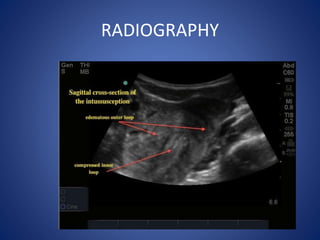

RADIOGRAPHY

• Plain X-ray Abd.: Bowel obstruction with absent caecal

shadow gas in ileo-ileal & ileo-colic cases.

• Ba-enema: the claw sign in ileocolic & colocolic cases.

• CT scan in equivocal cases of ileo-ileal intussusception. (small

bowel mass may be revealed)